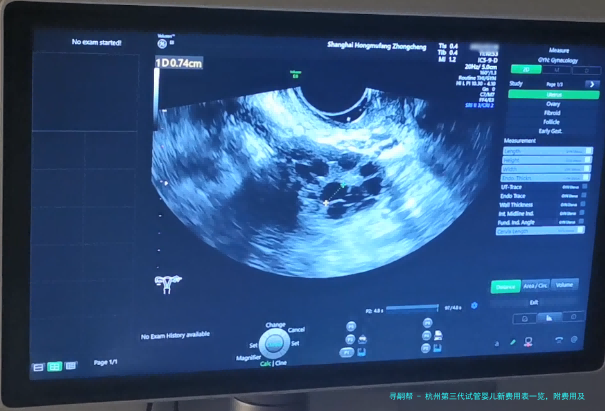

为了提高试管婴儿的成功几率,需要在此前做好相关的身体检查,防止有不利于试管婴儿操作的因素存留。两边的主要检查项目存在:血检、甲状腺整套功能、性激素六项检查、子宫B超检查、阴道分泌物检查、HPV检查、支原体检查、衣原体检查、卵巢功能评估AMH检查、精液常规检查等。